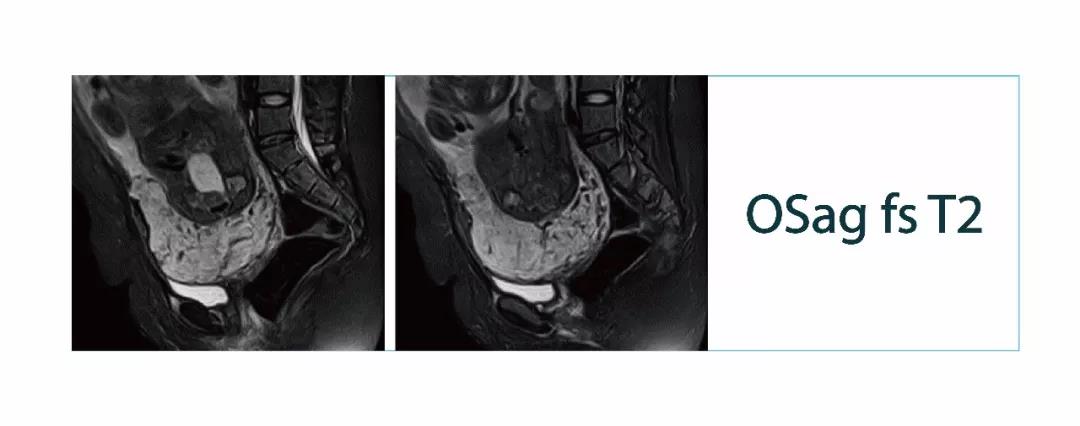

【有声病例】后交叉韧带断裂